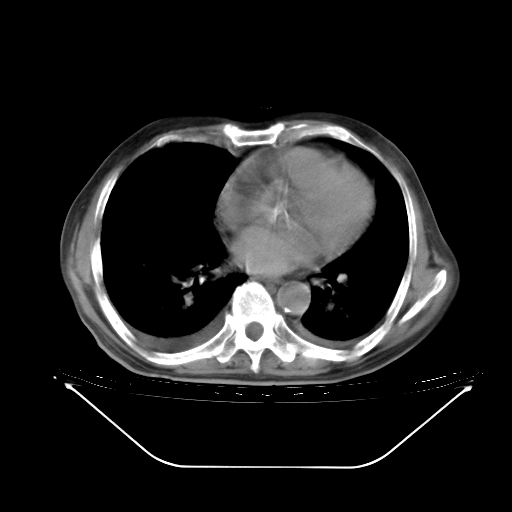

今天复查肺部CT,发现双肺广泛磨玻璃样改变。所以我把3月19日和5月9日相隔50天的肺部CT上传。请大家会诊。

2009年3月19日肺部CT片。

5月9日肺部CT(在4月27日齐鲁医院肺部CT描述部分肺组织磨玻璃样改变,12天后肺组织广泛磨玻璃样改变)

大致读了系列胸部CT:纵隔窗无明显异常,肺窗:从4、27至今:主要是双肺中下野外带可见毛玻璃样改变,目前处于急性肺泡炎阶段,至于原因考虑1、结替组织或胶原血管性疾病所致?2、恶性疾病如恶组在肺部所致的表现或细支气管肺泡癌?3、药物或其它原因如肺蛋白沉着症所致肺泡炎目前不太可能?总之,明天就去请我院的呼吸科、感染科、血液科和临免专家会诊哈。